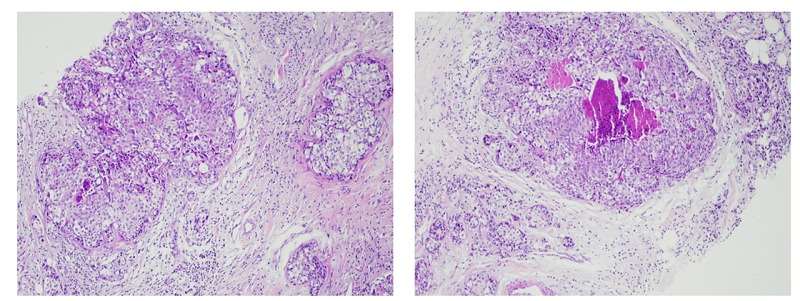

Sinh thiết tuyến vú trái kết luận Carcinoma (ung thư biểu mô) thể ống xâm nhập, type không đặc biệt, độ II (Ảnh: BSCC)